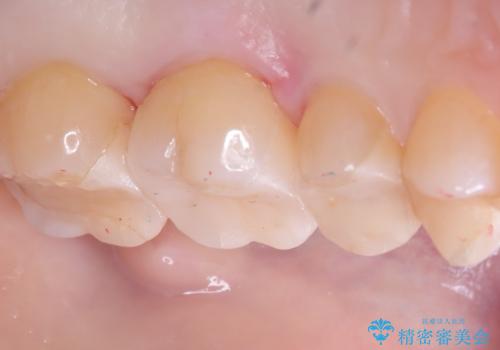

- 主訴:詰め物が欠けてしまった。

歯冠色インレーが一部欠けてしまい、他院にて部分的に樹脂のコーティング剤を付けてもらっている状態でした。

欠けている大きさが大きかったため、やり替えを提案しセラミックインレーでのやり替えとなりました。

他院にてセットしたセラミックインレーの一部が研磨では対応できない程大きく欠けてしまっていたため、やり替えとなりました。再度欠けぬよう、歯質を削り厚みを確保しています。